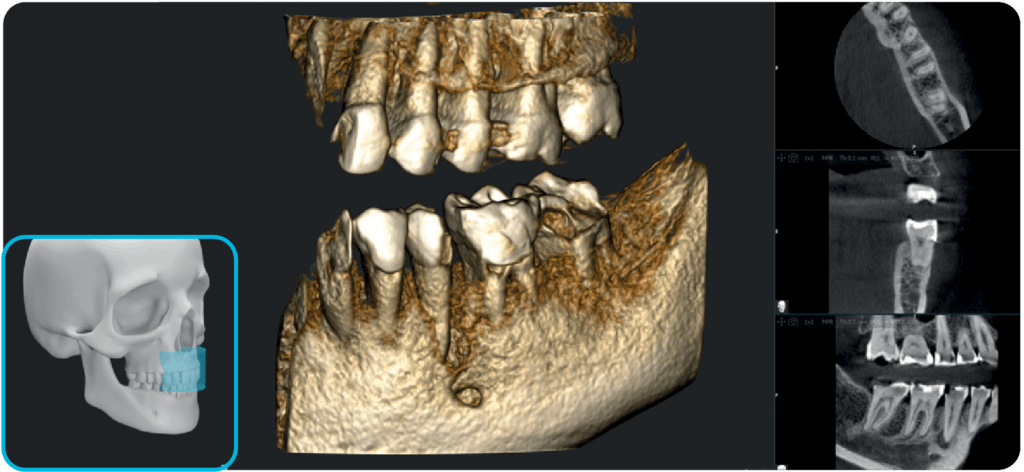

Dzięki szerokiemu zakresowi pól obrazowania (FOV) od 5×5 cm do 17×12 cm (Ø x H), urządzenie znajduje zastosowanie w różnorodnych zabiegach stomatologicznych – sprawdzi się zarówno w stomatologii ogólnej, jak i w specjalistycznych dziedzinach, takich jak implantologia, endodoncja, ortodoncja czy chirurgia szczękowo-twarzowa.

Przydatne w chirurgii implantologicznej i w stomatologii ogólnej jako badanie ograniczone do pojedynczej szczęki.

Stosowany w większości przypadków zabiegów z obszaru chirurgii jamy ustnej, w tym jednocznesnego wszczepiania wielu implantów.

Oprogramowanie RealGuide 5.4 wykorzystuje technologię AI, aby maksymalnie ułatwić i usprawnić pracę lekarzom na każdym etapie leczenia implantoprotetycznego, zapewniając lepszą komunikację z pacjentami, budując zaufanie i poprawiając wskaźniki akceptacji leczenia.

Upraszczając złożone zadania i automatyzując kluczowe procesy, oprogramowanie usprawnia cały proces, umożliwiając szybsze i dokładniejsze planowanie leczenia.

Segmentacja zębów

Segmentacja kości

Pozycjonowanie implantu